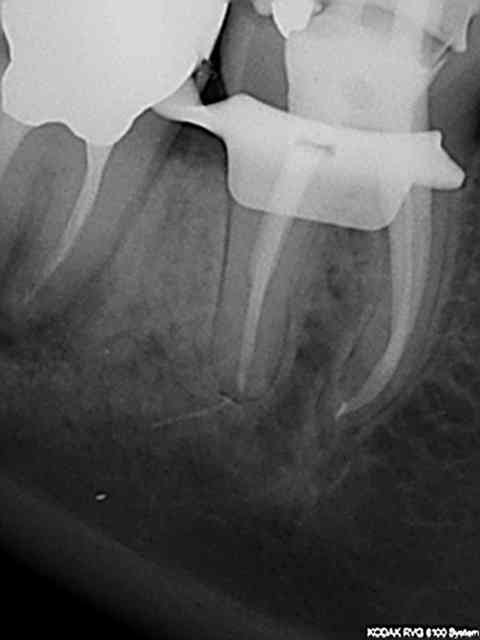

J'ai vu une patiente le 21 mai 2013 pour un traitement endo sur 27 qui devait être suivi d'une prothèse. Après le traitement il n'y a plus eu de suivi de la part de la patiente jusqu'au 25 novembre. La dent n'avait plus de pansement depuis un moment et une légère sensibilité à la percussion.

J'ai décidé de reprendre le traitement à la CRAC ! un protaper cassé.

Pff. Ca arrive à tout le monde de péter un instrument. J'ai également eu un souci tout a l'heure, un R25 a pété à son 10 ème canal de traité.

Le bout de Niti est très bas impossible à déloger ;au mieux un bi-pass mais cela en vaut-il le coup:les risques de LIPOE